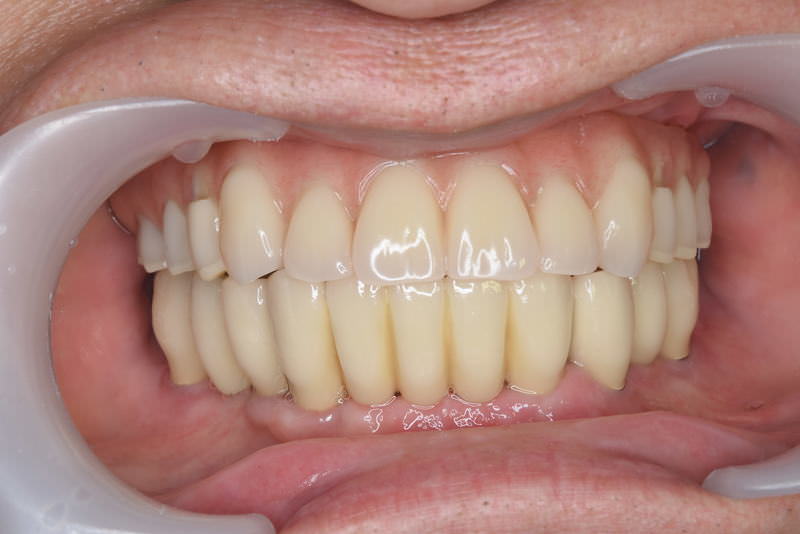

症例140代 男性 主訴 奥歯に歯を入れたい、しっかり噛みたい

治療前

治療後(5年経過)

※説明

主訴 奥歯がない為、食事が不自由である。入れ歯は煩わしいので、固定制のインプラントにして欲しいと訴え来院。口腔内全体で6本のインプラントを埋入。仮歯にて神経筋機構、顎関節のバランスを整え、リハビリを経て、約5ヶ月後にジルコニアを装着。

リスクとしては、外科的侵襲がある。デメリットは、保険外診療の為、経済的負担がある。

費用 316万(税込) (オペ・仮歯・最終補綴物まで含む)